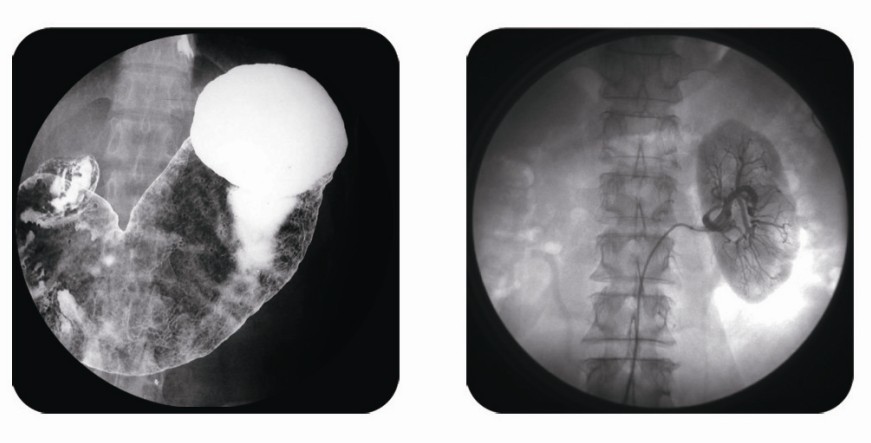

傳統胃腸造影檢查,病變顯示率低,輻射劑量大。普朗醫療器械公司生產的幾款多功能腸胃造影x光機,更能滿足不同等級不同規模的大小醫院選擇,從臨床及科研都很好。尤其最新的PLD8800多功能腸胃造影x光機用途更為廣泛。多功能腸胃造影x光機是目前各大醫院最普及的且用途最廣的一種X光機。普朗醫療的胃腸機功能多,簡便易用,能保證圖像質量,該機采用高制式電視系統,優秀的數字化系統能使多功能腸胃造影x光機的性能得到提高,應用范圍獲得極大的拓寬。

如果您想了解多功能腸胃造影x光機價格多少錢,普朗醫療作為多功能腸胃造影x光機品牌廠家,報價肯定會比進口產品要優惠很多。具體詳情,您可以點擊頁面漂浮的在線客服圖標,進行在線咨詢。同時,普朗醫療也可以給您簡單介紹一下關于多功能腸胃造影x光機的主要臨床應用:

1、一般應用:數字透視,動態及多方位觀察器官病變,圖像更清晰,并可保留末幀圖像;既可使用暗盒完成常規X線拍片,這是其最大的優勢,拍片質量大大提高。

2、特殊檢查的應用:如“T”管造影、消化道鋇餐、靜脈腎盂造影、子宮輸卵管碘油造影等,在實時監視的同時隨時采集,抓住關鍵圖像,并可連續采集,電影回放整個過程。

3、介入方面的應用:能很好開展全身各部位的血管造影、藥物灌注、栓塞治療及經皮穿刺活檢引流,主要應用于血管造影診斷及腫瘤的治療,不明原因腫塊的性質確定。